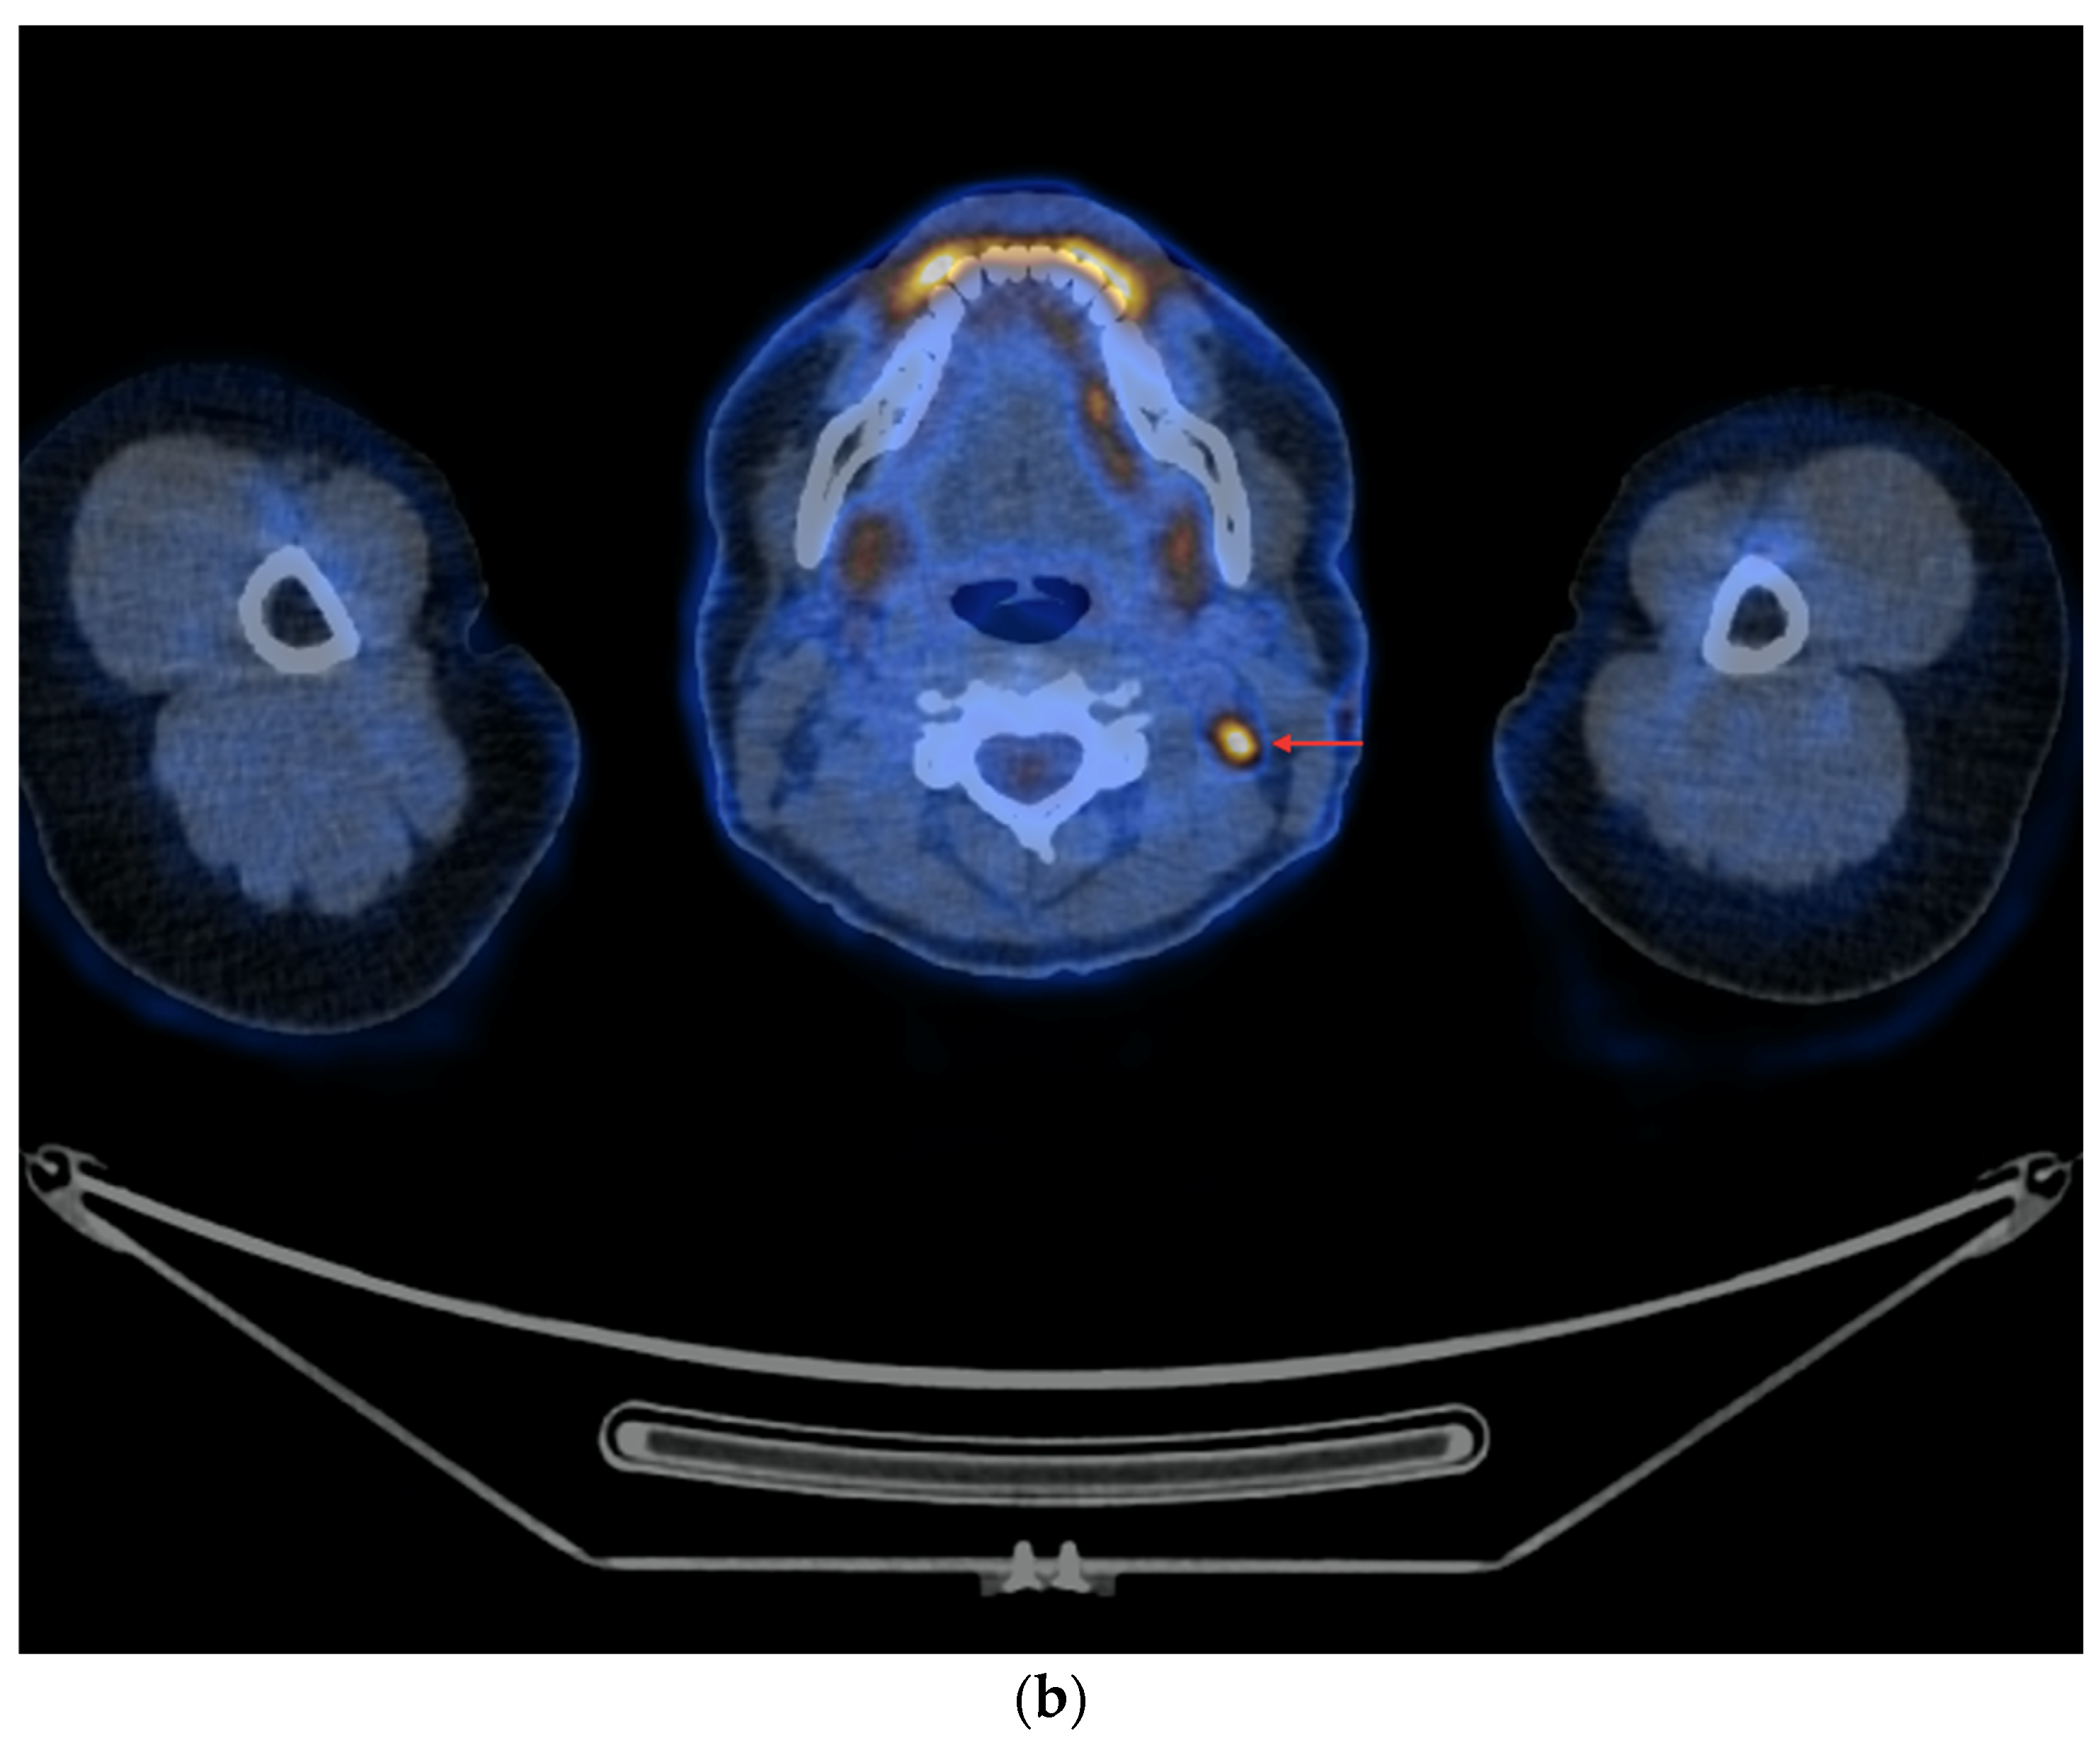

- In the case of non-resectable lesions (due to a lack of the patient’s consent to repeated surgery, lack of technical possibilities of surgery or other reasons), the lesions were verified using FNA only, and after verification, the patients remained in the observation group or were referred to tyrosine kinase inhibitor (TKI) therapy (Figure 4a,b).

Figure 4. PET/CT with [18F]FDG (a) Maximum-intensity projection (MIP). (b) Axial fusion projection. These show an example of accumulation of the [18F]FDG in the left retroesophageal lymph node (red arrow). The lesion was verified as being metastasized DTC using FNA. Due to comorbidities and the patient’s lack of consent, resection of the lesion was abandoned; the patient was left in the observation group, with a stable Tg concentration in follow-up determinations (maximum natTg concentration 3.91 ng/mL, maximum sTg concentration 19.62 ng/mL).